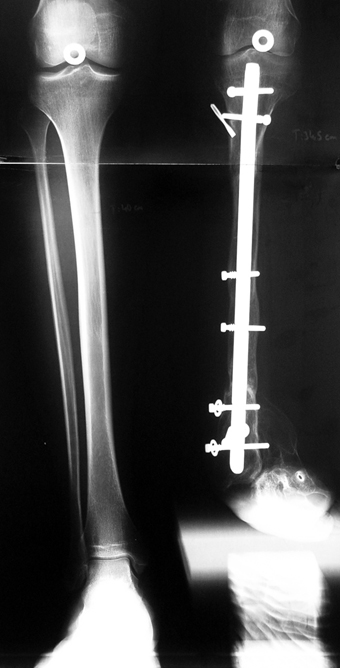

3. POSTTRAUMATIC LOWER LIMB SHORTNESS (MALUNION)

This type of shortness occurs after a fracture heals in a shortened position. Most cases are seen in adults and can be treated with one lengthening operation. Additional deformities can be corrected simultaneously. Most of these cases can be treated with lengthening over nail or just corrections and intramedullary nailing.